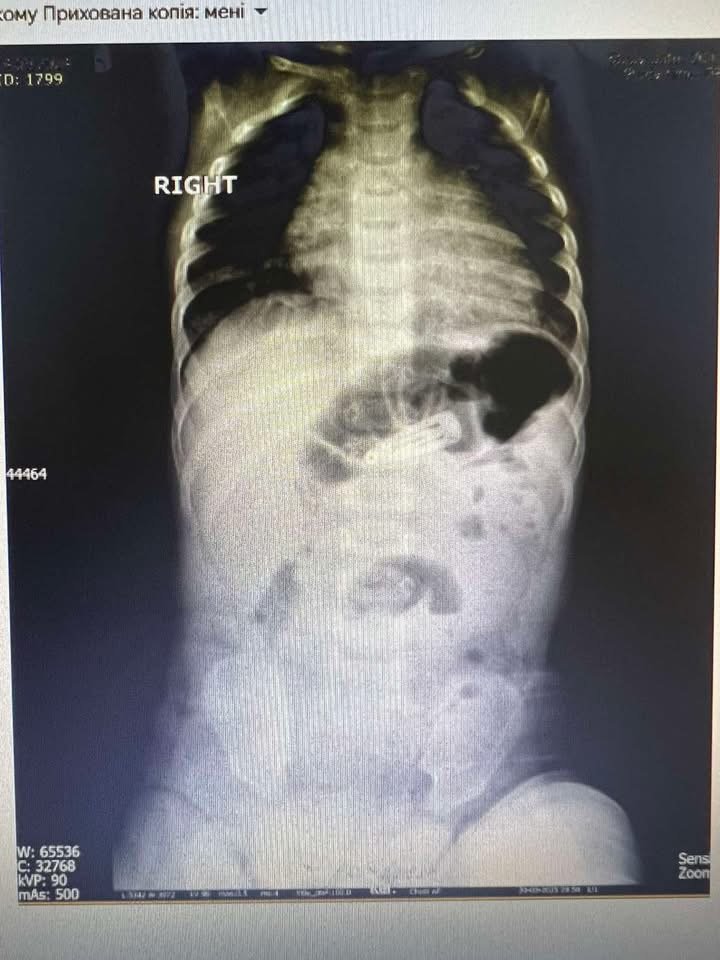

Унікальний медичний випадок стався в Мукачеві: в обласній дитячій лікарні лікарі провели ендоскопічне видалення заколки для волосся зі шлунка 6-місячної дитини. Це перша така процедура на Закарпатті, виконана без відкритого хірургічного втручання, що могло б становити загрозу для життя малюка через його вік і вагу.

Замість скальпеля — ендоскоп: завдяки командній роботі хірургів, анестезіологів та ендоскопістів, дитину вдалося врятувати швидко, безболісно та без ускладнень. Зараз малюк вже почувається добре.